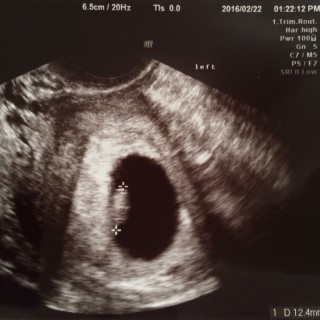

体外受精(凍結胚移植5日目胚盤胞)で授かりました。 D28/BT10妊娠判定hCG691。 5w5d胎嚢確認GS16.7mm。 7w2d心拍・心音確認CRL12.4mm。 たくましくドックンドックン動く心音を聞かせてもらって感動しました。 母子手帳も貰い8w2dにクリニック卒業です。